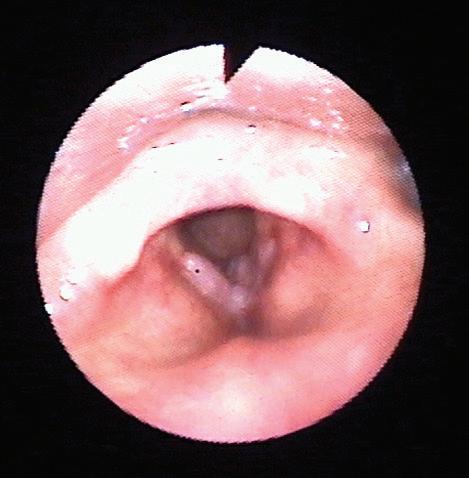

като засягане на ларинкса има при по -

от 95% от пациентите, при ларингоскопия се наблюдават характерните брадавицовидни формации (Фиг. 1. и Фиг. 2). Засягане на трахеята без ларингеални лезии се среща рядко и при тези случаи диагностичен метод на избор е бронхоскопията. Вземането на материал от лезиите за патохистологично изследване е от съществено значение за хистологично потвърждение на диагнозата. Биопсията е необходима както за типизация на вируса, така и за да се потвърди или изключи злокачествена трансформация.